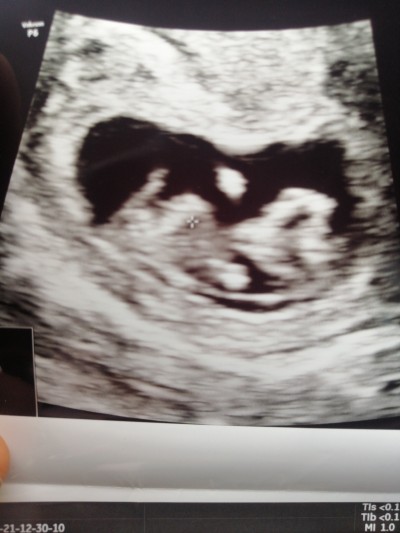

Bu post eda güneş için açılmıştır cinsiyet tahmini :D

hade kurban senin için post açtım bursa kalacak

Askom bas bas bagriyo erkegim ben diye :DD

Kız istediğin haber vermek olsun annemden bacımdan önce sana haber vericem söz veriyorum canısı :D

Hahahaha benimkinin pipisi kısa bacım :D